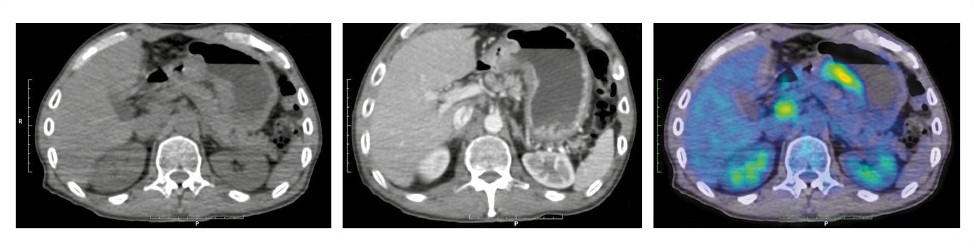

Для уточнения распространенности опухолевого процесса выполнена ПЭТ/КТ с 18F-ФДГ. На большом участке малой кривизны обнаружена опухолевая ткань с выходом за пределы серозной оболочки в парагастральную клетчатку с гиперфиксацией радиофармпрепарата (РФП), стандартизированный коэффициент максимального накопления SUVmax равен 14,4. Определяются увеличенные парагастральные, чревные, а также забрюшинные лимфоузлы (л/у) протяженностью до бифуркации аорты (SUVmax 5,9); рис. 1.

Рис. 1. Пациент Т., 54 года. На аксиальных КТ без и с контрастным усилением, а также ПЭТ/КТ-проекциях по малой кривизне желудка определяется протяженная гиперметаболическая опухолевая ткань – SUVmax 14,4 с переходом за границы стенки желудка в парагастральную клетчатку, образуя конгломерат с увеличенными парагастральными и чревными л/у до 15 мм с гиперфиксацией РФП, SUVmax 7,5, прекавальный и забрюшинные л/у до бифуркации аорты – до 15 мм, SUVmax 5,9.